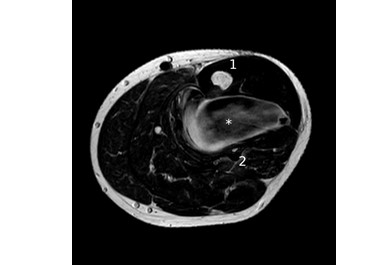

Case report. A 26 years old male presented with a painful swelling on the left lower leg with no history of recent trauma. An Magnetic Resonance Imaging (MRI) prompted by the general practitioner had showed a homogenous mass anterior to the fibula with contact to the bone and vascular structures (Figure 1). The radiologist‘s first suspicion was a highly vascularized tumour with the diffential diagnosis of an infected hematoma. The patient was referred to our department of vascular surgery.

Fig. 1. MRI (axial, T2) of the lower leg, 15 cm distal to the knee joint space (image courtesy of Radiologie 360°): (1) tibia, (2) fibula, (*) «tumor».